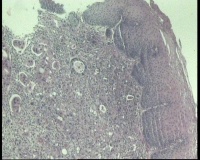

食道:距门齿37厘米至贲门见不规则增生性肿物,约环1/2周食管腔,表面充血糜烂,质硬,易出血。齿状线尚清晰,距门齿41厘米

鳞状上皮下见异型腺体,部分区域腺腔不明显,病变位置距门齿37厘米,齿状线尚清晰,报食管腺癌(中—低分化)吗?胃镜考虑食管Ca累及贲门